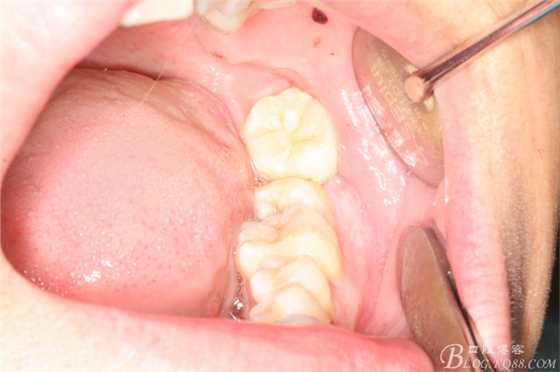

圖4.患者的口內(nèi)影像檢查:右側(cè)47萌出少,合向脫位間隙亞種不足